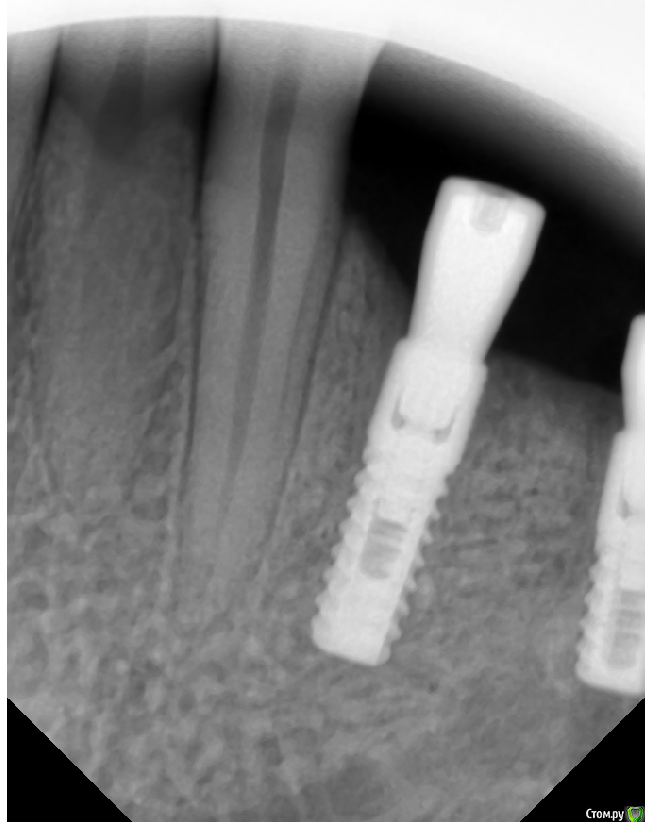

Sergiosse Опубликовано 4 декабря, 2019 Поделиться Опубликовано 4 декабря, 2019 Установил три импланта , средний вплотную к н.ч. каналу. После формирования ложа при зондировании перфора не было . на следующий день после операции онемение в области угла рта не проходит . Думал что из-за отёка. Сегодня пятый день. Изменений нет. Сильных болей нет , хотя пациентка принимает Кетонал. Пациентка сейчас в Москве , я я хочу попросить её чтобы она дошла до хирурга и на пару оборотов выкрутила средний имплант . вопрос Нужно ли это делать , как удостовериться, что это именно из—за импланта,сделать Кт? Отслойку лоскута делал осторожно,к выходу нерва не приближался , кровотечение и боли во время операции не было . Я думаю может быть медсестра (новенькая , неопытная )фарабефом придавила?=48001:тазеева2.png] Ссылка на комментарий

Dmitry DK Опубликовано 8 декабря, 2019 Поделиться Опубликовано 8 декабря, 2019 Если вы все сделали по "инструкции" ( которая у вас на КТ ), наверняка имплантат оказался вплотную к каналу, но не думаю, что вы в него погрузились, но КТ нужно сделать для перестраховки.Скорее всего - фрезой залезли в канал ( он не обязательно должен кровить ), в таком случае выкручивание имплантата не поможет. Вопрос в том как сильно был поврежден сосудисто-нервный пучок, от этого будет зависеть динамика Ссылка на комментарий

Sergiosse Опубликовано 16 декабря, 2019 Автор Поделиться Опубликовано 16 декабря, 2019 В продолжение истории. Жалоб кроме, как на онемение нет. витамин В12 назначил. Думаю,продавил имплантом стенку канала,кагда давал торк. Через неделю увижу пациентку,какая дальнейшая тактика? Под нагрузкой от коронки не будет болей? странная верхняя стенка канала, с размытыми границами, остеопорз? Ссылка на комментарий

Дмитрий М Опубликовано 18 декабря, 2019 Поделиться Опубликовано 18 декабря, 2019 Мнения разделились. Вопрос: удаление импланта улучшит ситуацию? Выдавленная костная стенка всё равно останется внутри канала . Может быть лучше его выкрутить на пару оборотов ?что вам даст выкручивание на пару оборотов? по снимку не видно что имплантом провалились в канал, возможно только фрезой во время препарирования, и получили гиперкомпрессию от гемптомы в канале. возможно дело даже не в среднем импланте.покажите срезы ментального отверстия. после операции онемение в области угла рта не проходиттак понял, вы проводниковую анестезию делали? и во время операции пациент ничего не почувствовал, возможно ли что задели его во время отслойки лоскута? Ссылка на комментарий

Dmitry DK Опубликовано 27 декабря, 2019 Поделиться Опубликовано 27 декабря, 2019 Винт не в канале, очевидно, что фрезой задели. Выкручивание ничего не даст ( на нерв не давит). Удалять на случай разборок... Зачем?... Если разбор реально будет, на КТ все видно. Не переживайте, все наверняка восстановится через месяца 4, последней фрезой до нижней стенки вы видимо не дошли Ссылка на комментарий